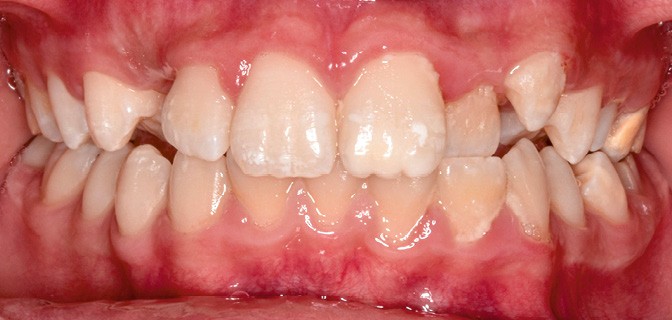

L’examen clinique montre une MIH sévère sur 16, 26, 36 et 46, et modérée sur 11 et 21.

Sur le plan alvéolo-dentaire (fig. 1b) :

- Classe II subdivision gauche avec déviation du point inter-incisif mandibulaire à gauche ;

- occlusion inversée entre 22 et 32 ;

- dysharmonie dento-arcade (DDA) sévère ;

- 13 en position haute retenue.